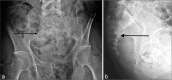

(a and b) Frontal and lateral radiographs of the sacrum. Destructive lytic lesion sacral lesion, with better demonstration on the lateral view (black arrows).